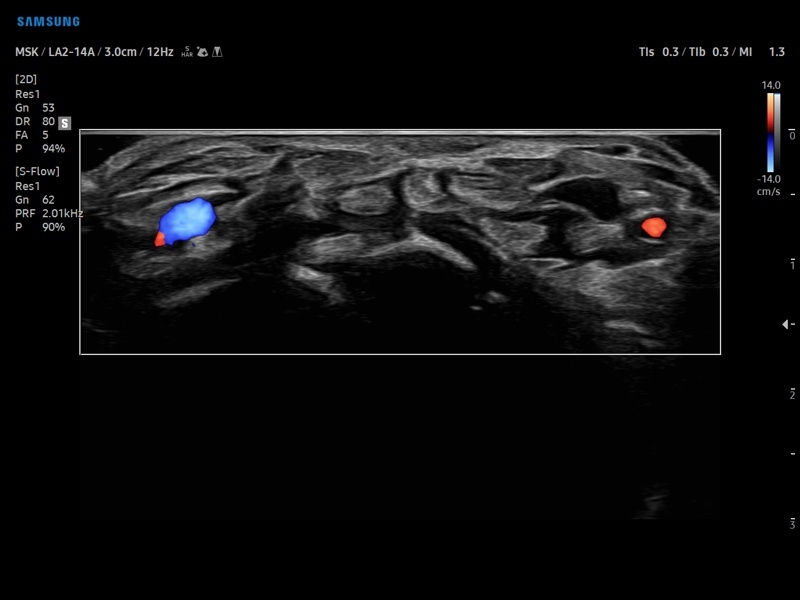

• Диагностика костно-мышечной системы

• Модуль NerveTrack – автоматическое определение срединного нерва в поперечном сечении с использованием искуственного интеллекта.

• Сонные артерии:автоматическая, полуавтоматическая, ручная трассировка доплеровского спектра; ПСС, КДС, %СтПлощ, %Ст Диам, площадь сосуда, диаметр сосуда, средняя толщина интимы, объемный кровоток.

• Артерии верхних конечностей:автоматическая, полуавтоматическая, ручная трассировка доплеровского спектра; ПСС, КДС, %СтПлощ, %Ст Диам, площадь сосуда, диаметр сосуда, объемный кровоток.

• Артерии нижних конечностей:автоматическая, полуавтоматическая, ручная трассировка доплеровского спектра; ПСС, КДС, %СтПлощ, %Ст Диам, площадь сосуда, диаметр сосуда, объемный кровоток.

• Вены нижних конечностей:автоматическая, полуавтоматическая, ручная трассировка доплеровского спектра; максимальная скорость, диаметр сосуда.